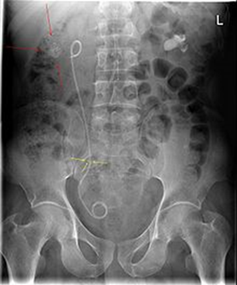

• Splint (dubbel JJ-stent) alt Nefrostomi. Vid avstängd pyelit

o Splint (bilden) via urinröret till blåsen, sedan till uretärostiet, guidevajer till njure och sedan slang, när vajern dras ut krullar slangen till sig i njure (och även kringla i blåsan) och urin leds ut via denna slang